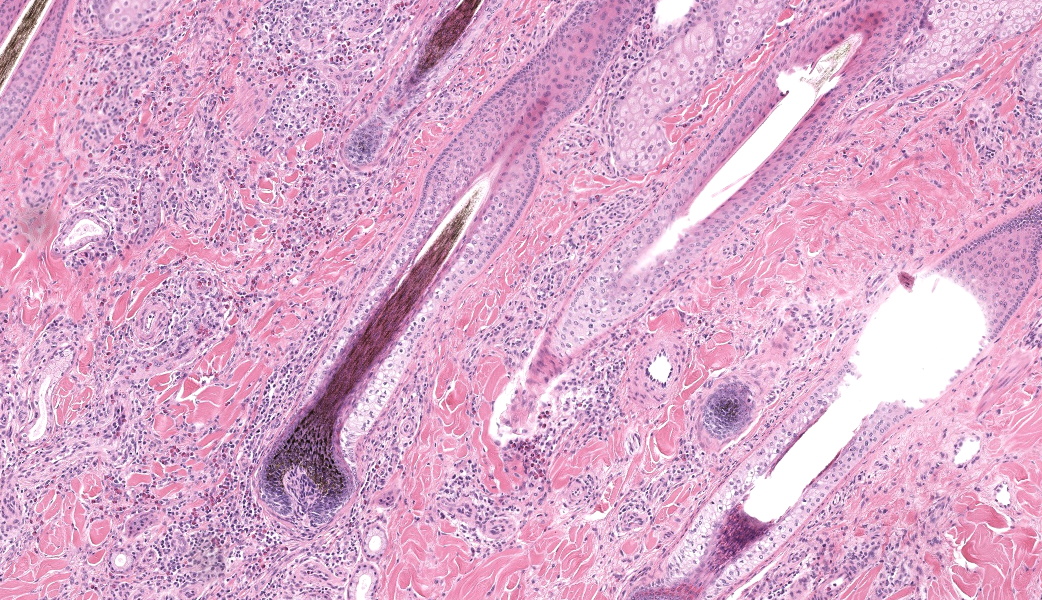

Haired skin, coronary band. Expanding and infiltrating the entire dermis are multifocal to coalescing perivascular, periadnexal and interstitial aggregates of moderate numbers of lymphocytes, eosinophils and histiocytes, fewer plasma cells and occasional neutrophils. Multifocally within dermis are few small areas of intensely eosinophilic, fragmented collagen fibers admixed with eosinophilic cellular- and basophilic nuclear debris, surrounded by epitheloid macrophages and multinucleated giant cells (eosinophilic granulomas). Intramurally and intraluminally within multiple hair follicles are moderate numbers of eosinophils, lymphocytes and histiocytes and few multinucleated giant cells (mural and luminal folliculitis), and adjacent follicular epithelium display moderate spongiosis. In the dermal-epidermal interface, there is a multifocal mild edema. The epidermis shows mild lymphocytic infiltration, mild spongiosis and occasional apoptotic keratinocyte, diffuse mild acanthosis and mild rete ridge formation (epidermal hyperplasia), moderate parakeratotic and orthokeratotic hyperkeratosis and multifocal erosions and ulcerations, the latter being covered by large serocellular crusts spanning over several adnexal units. Serocellular crusts show abundant viable and degenerated neutrophils, occasional eosinophil, cellular debris, fibrin, free keratin and hair fragments and occasional small basophilic bacterial colonies. There are also small epidermal intracorneal pustules multifocally. Several arteriolar walls in deep dermis show infiltration of few eosinophils and lymphocytes (vasculitis). The deep dermis displays mild diffuse edema.Contributor's Morphologic Diagnoses:

Haired skin, coronary band: Dermatitis and folliculitis, lymphoplasmacytic, histiocytic and eosinophilic, multifocal to coalescing, moderate, with eosinophilic granulomas, epidermal intracorneal pustules, serocellular crusts and orthokeratotic and parakeratotic hyperkeratosisEquine multisystemic eosinophilic epitheliotropic disease (MEED)